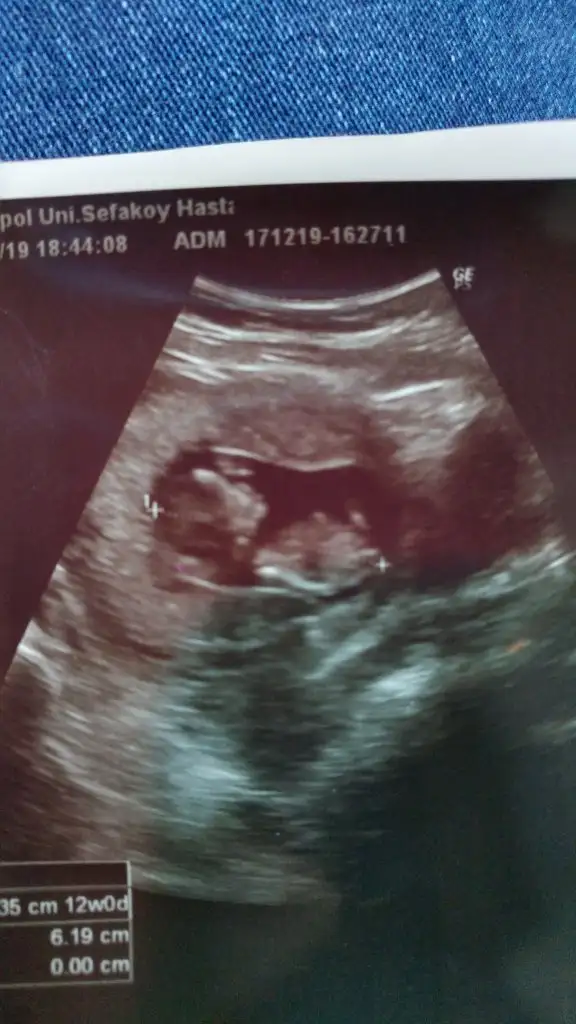

Ikra meyra Ikra meyra canım burda 12+2 ultrasona göre. Tekrar gönder demiştin var mı acaba bi şansım bu sefer 😂

• IMG-20191218-WA0017.webp

IMG-20191218-WA0017.webp

14,8 KB · Görüntüleme: 89

• IMG-20191218-WA0018.webp

IMG-20191218-WA0018.webp

15,9 KB · Görüntüleme: 100